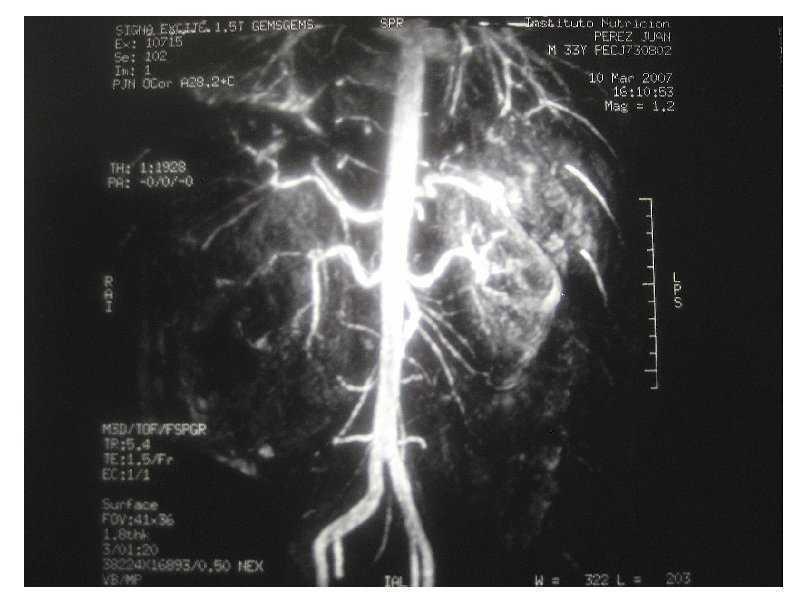

Una vez en mejor estado general se realizó tomografía axial computarizada que mostró una imagen de un tumor renal derecho de 10 UH heterogéneo que desplazaba en sentido posteroinferior y medial al riñón (Imagen 1). Las dimensiones del tumor fueron de 15 cm en sentido longitudinal y 10 cm en sentido transversal, de características heterogéneas con un refuerzo de -30 UH al administrar medio de contraste, lo que aumentó la sospecha de angiomiolipoma renal. Se realizó resonancia magnética con reconstrucción vascular, en la cual se observó hiperintensidad en T1, isointensidad en T2, sin delimitar el tumor y con sangrado con dimensión aproximada de 6-7 cm de diámetro (Imagen 2). En la angiorresonancia se observó pobre vasculatura, incrementando la sensibilidad diagnóstica para angiomiolipoma (Imagen 3).

Imagen 1. TAC abdominal simple.